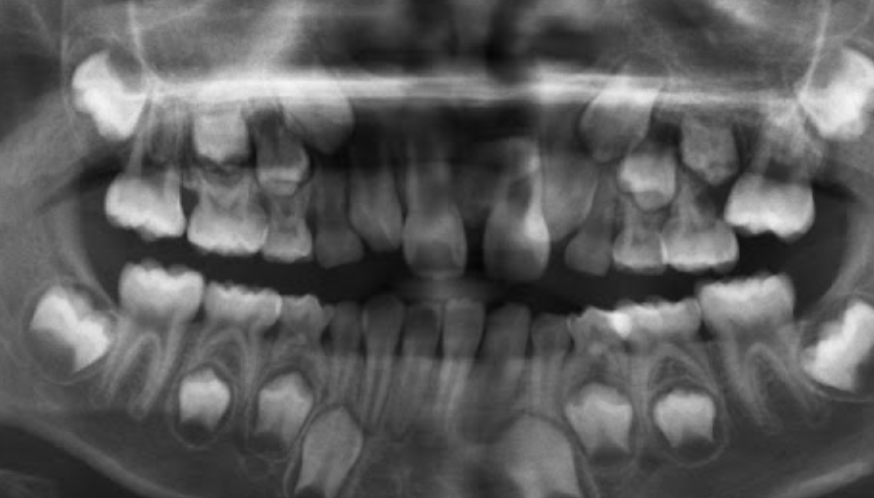

1.Ad. LOWER central incisors present? Yes. definitely 6-7 or older

1. Ad. UPPER CI present? Yes def. 7-8 y.o

3.Ad. Upper LAT incisor present (baby sheds 7-8)? NO so still under 7-8

Conc: pt is under 7